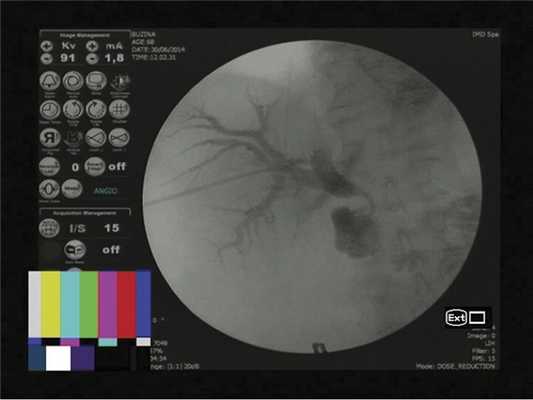

Учитывая данные эндоскопического обследования, невозможность выполнения эндоскопической ретроградной паткреатохолангиографии (ЭРХПГ) вследствие выраженного стеноза постбульбарного отдела ДПК, для устранения билиарной гипертензии выполнено формирование чрескожной чреспеченочной наружно-внутренней холангиостомы (рис. 5).

Рис. 5. Рентгенологическая картина установленного наружно-внутреннего дренажа. Контрастное вещество Омнипак в разведении 1:1.

С помощью иглы Chiba по правой аксиллярной линии в межреберье выполнена поисковая пункция правой доли печени, визуализирован правый передний секторальный проток, далее струна-проводник проведена во внепеченочные желчные протоки и просвет ДПК. По ней выполнено бужирование холангиостомического канала до 9 fr, низведен наружно-внутренний дренаж типа pig tail в просвет ДПК, по которому стала выделяться ахоличная желчь с примесями нитей фибрина. Холангиостома проверена на проходимость, фиксирована к коже.